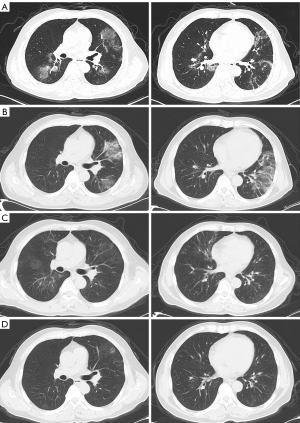

A 58-year-old man was enrolled in a clinical trial of anti-CD19 CAR T cell therapy (ChiCTR1800019622) as a refractory FL patient at our center in August 2020. The patient achieved CR with anti-CD19 CAR T-cell therapy. The patient maintained CR status without receiving any maintenance therapy. He was first diagnosed with COVID-19 and fever in January 2023 without receiving a vaccine against severe acute respiratory syndrome coronavirus 2 (SARS-CoV-2). The patient recovered quickly after a simple symptomatic therapy. Unfortunately, he developed COVID-19 for the second time in April 2023. He presented with symptoms of hyperpyrexia, dyspnea, coughing, and shortness of breath. The patient’s oxygen saturation was approximately 88–92% without oxygen inhalation. He had a positive test for SARS-CoV-2 (reverse transcription-polymerase chain reaction). The C-reactive protein (CRP) was 36.2 mg/L and interleukin (IL)-6 was 658 pg/mL, respectively. He had B-lymphocyte deficiency (expression of CD19 in B-lymphocytes in the peripheral blood was 3.42%) and hypogammaglobulinemia (12.3 g/L). Computed tomography (CT) performed on admission revealed interstitial pneumonia in both lungs (Figure 1A). This patient received Paxlovid, molnupiravir, methylprednisolone (80 mg, daily for 14 days), tocilizumab (4 mg/kg, daily for 3 days), and symptomatic treatment; however, the symptoms of dyspnea and hypoxemia were not relieved, and SARS-CoV-2 remained positive. In the following 4 months, he had persistent hypoxemia and persistent positive SARS-CoV-2 test, although he received continuous oxygen therapy and methylprednisolone (40–60 mg, daily) therapy.

He was readmitted to our hospital in August 2023 with severe hypoxemia, dyspnea, and shortness of breath. He had an oxygen saturation of 82–88% without oxygen inhalation. The CRP was 60.5 mg/L, IL-6 level was 471 pg/mL, and SARS-CoV-2 tested was positive. Interstitial pneumonia worsened, with multiple spots and ground-glass shadows in both lungs (Figure 1B). He was diagnosed with post-COVID-19 syndrome (over 12 weeks since infection) (10). Bronchoscopy revealed airway inflammation after hospitalization. No evidence of bacterial, fungal, or tuberculosis infections other than SARS-CoV-2 was detected in the alveolar lavage fluid. The patient was administered molnupiravir and methylprednisolone (160 mg daily for 14 days). However, hypoxemia and interstitial pneumonia progressed. Oxygen saturation was at 85–88% without oxygen inhalation. The SARS-CoV-2 tested was positive at this time. The patient subsequently received ruxolitinib (5 mg, twice daily) as salvage therapy in combination with a gradually reduced dose of methylprednisolone from September 2023. The CRP was 38.3 mg/L, and IL-6 was 49 pg/mL, respectively, at the beginning of salvage therapy. After 2 months of ruxolitinib therapy, oxygen saturation recovered to 92–96% without oxygen. Methylprednisolone was discontinued. CT showed that his interstitial pneumonia was significantly better than before salvage therapy (Figure 1C). At this point, the SARS-CoV-2 expression was negative. The CRP was 15.2 mg/L and IL-6 was 18.4 pg/mL, respectively (Table 1). Throughout the course of ruxolitinib therapy, the patient did not develop any degree of hemocytopenia. Two months later, he was diagnosed with COVID-19. However, his interstitial pneumonia did not progress again, and symptoms such as dyspnea did not recur (Figure 1D). Ruxolitinib was discontinued after 6 months of salvage therapy, during which interstitial pneumonia did not progress again, and SARS-CoV-2 detection continued to be negative. The lymphoma was in a persistent CR state during multiple COVID-19 infections. After ruxolitinib therapy, the patient’s lymphoma remained in continuous CR for 17 months.